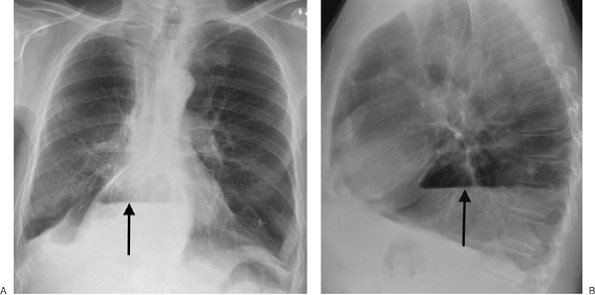

FIGURE 6-4. Morgagni hernia. PA (A) and lateral (B) chest radiographs show colon, filled with air and stool (arrows), herniating into the anterior mediastinum through a congenital defect in the anteromedial diaphragm.